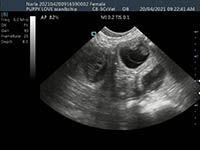

Mobile Ultrasound Pregnancy Scanning and Microchipping Services

Puppy Love scan and chip